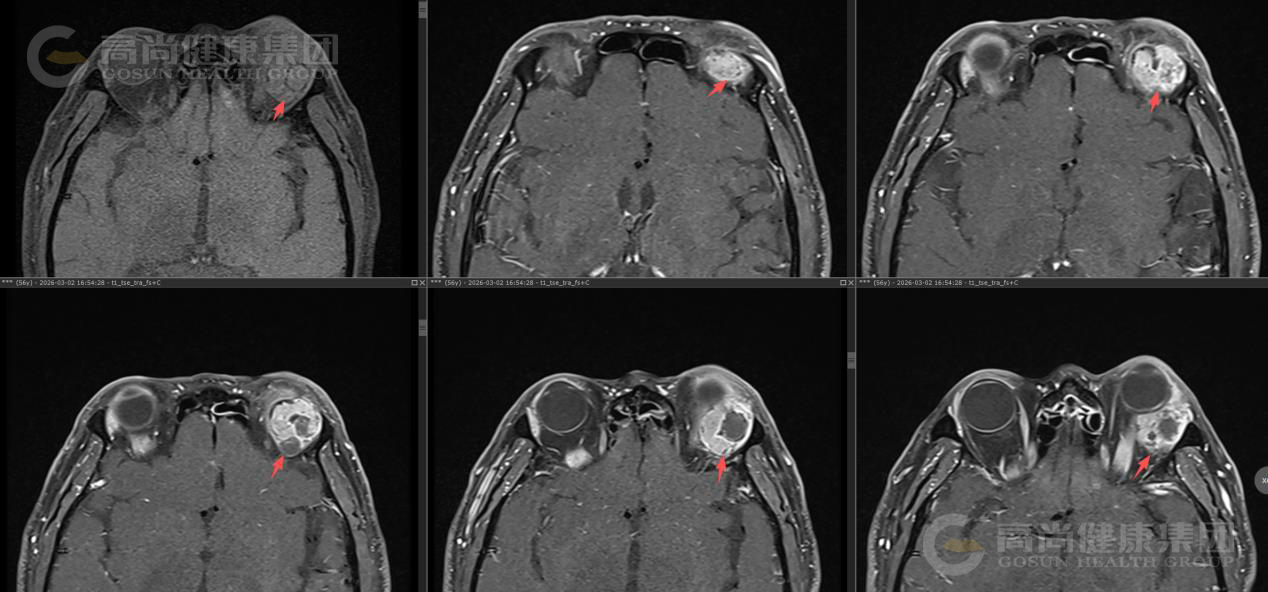

眼眶MR平扫+增强扫描

序列 T1WI T2WI T2WI-FS DWI/ADC T1-VIBE+C 3D-T1WI+C

方位 TRA SAG COR

左眼眶外上泪腺区类圆形异常信号影,大小约23×26×26mm(左右径×前后径×上下径),呈囊实性改,T1WI呈等信号,T2WI及T2WI-FS序列主要呈稍高信号伴囊样高信号,实性部分DWI呈轻度高信号,囊性部分呈等信号,ADC实质部分呈低信号,囊性部分呈高信号。

MR增强扫描: 肿块实质部分呈明显强化,且持续强化,囊变区不强化,病灶累及左眼眶肌锥内外间隙,与邻近泪腺界限不清,左侧眼球受压、向前突出,左侧上直肌、外直肌轻度受压。

影像诊断结果: 左侧泪腺区肿瘤性病变,考虑泪腺混合瘤,部分囊变坏死,不除外其它,请结合临床。